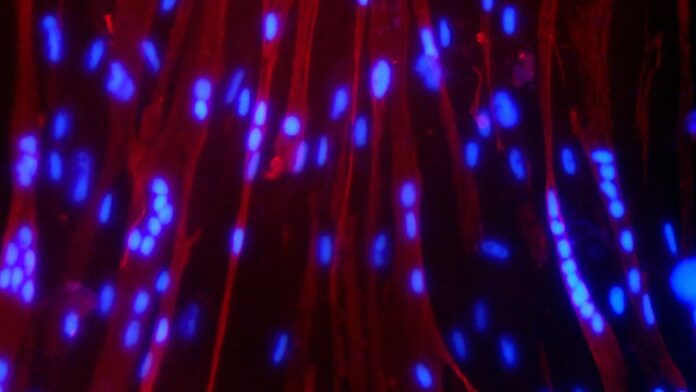

According to NASA’s official site, the Sprouts-ISRO investigation will germinate and grow greengram and fenugreek seeds aboard the ISS to study their development, genetics, and nutritional value in microgravity. Myogenesis-ISRO uses human muscle stem cell cultures to examine how spaceflight impairs muscle repair and mitochondrial metabolism, and tests chemicals to bolster muscle health during long missions. Space Microalgae-ISRO studies how green microalgae grow and adapt in microgravity, since rapidly growing, nutrient-packed algae could serve as a fresh food source and help recycle air and water on spacecraft.

Together, these space biology experiments could advance new ways to grow fresh food in orbit, maintain muscle mass during long missions, and even support treatments for muscle loss and nutrition on Earth.